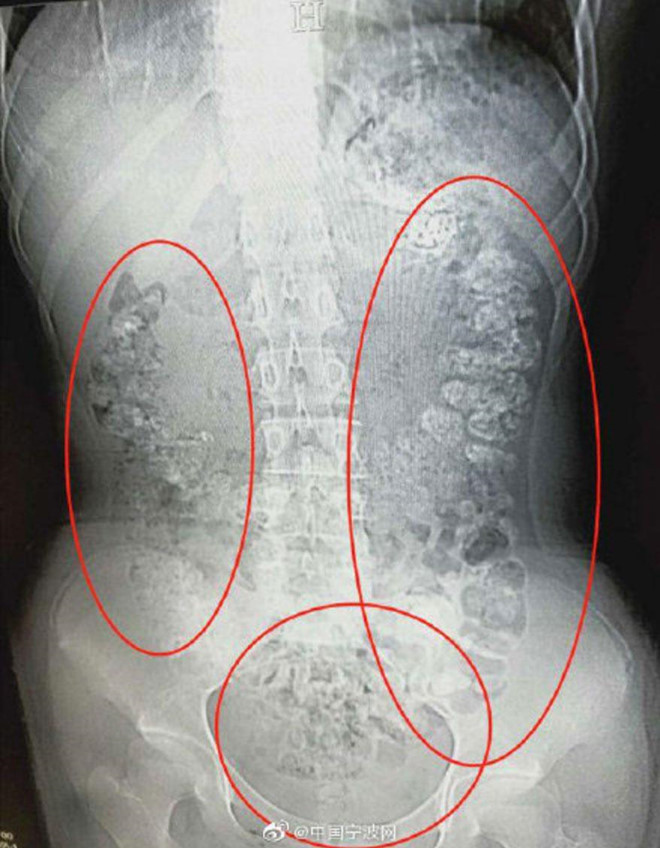

| Ảnh chụp X-quang cho thấy có hàng trăm viên trân châu nằm trong bụng bé gái. Ảnh: Sina. |